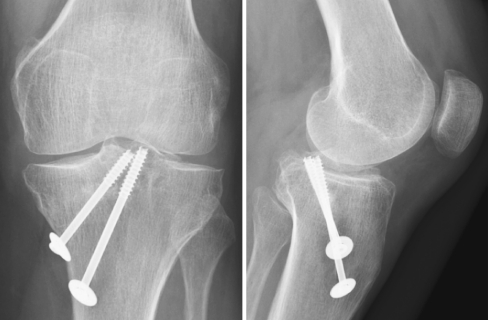

There was a good fixation and compression of the avulsed fragment. Radiographic evaluation demonstrated good positioning of the screws with all screw threads in the avulsed bony fragment (Fig. 5).

Fig. 5.

Standard radiographs showing positioning of the lag screws and complete disappearance of the pseudo-arthrosis of the bony avulsion of the tibial insertion of the PCL

Postoperatively, the patient was mobilized immediately with a full leg cylinder plaster cast. There was no weight bearing for the first 6 weeks followed by full weight bearing without the plaster cast. Mobilization was guided by a physical therapist. Three months after surgery, the patient was satisfied with the result of the surgical intervention. The complaints of a “clicking” sensation and posterior pain on weight bearing were completely resolved. Physical examination showed no posterior sag or anterior-posterior instability. Radiographs showed a complete disappearance of the pseudo-arthrosis of the bony avulsion of the tibial insertion of the PCL and good incorporation of the bone graft (Fig. 5).